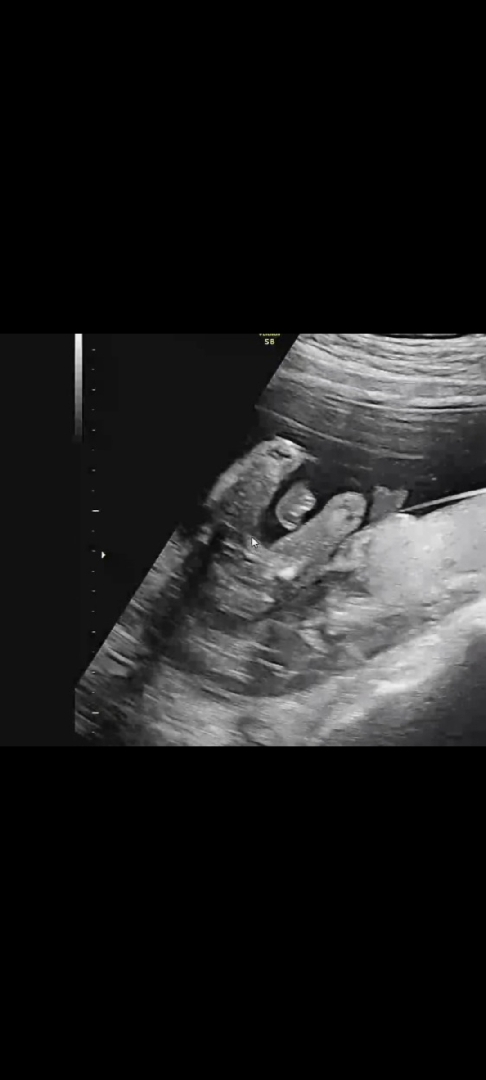

딸인가요??

16주차 초음파입니당

딸이네요